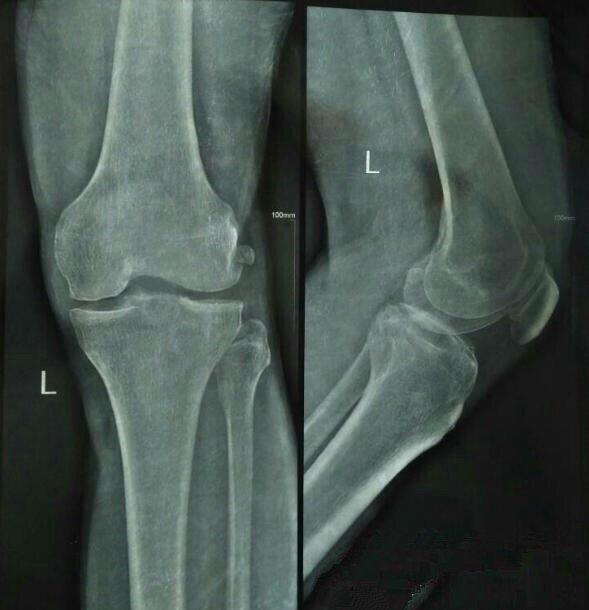

我先说说我家的情况吧,老家江西的,我爸今年45岁,6年膝盖骨质增生,基本上下不了床,每次下雨潮湿,冷点的天气就痛得牙齿直打哆嗦,我妈妈每次给他穿裤子的时候都叫的嗷嗷叫,过后还生气锤床板,试过针灸,推拿,热敷,还有很多很多其他的偏方,当时好了点,但不治根!